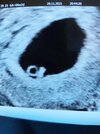

jeden z moich pęcherzyków się wchłonął (na pierwszym usg były 2 pęcherzyki ciążowe), więc nie będzie już bliźniaków... lekarz powiedział że to bezpieczniej i często tak się zdarza, tamten był dużo mniejszy. A wracając do wizyty, moja kruszynka ma 43 mm i serduszko już bije ❤ nawet je usłyszałam! Nie mogłam powstrzymać łez